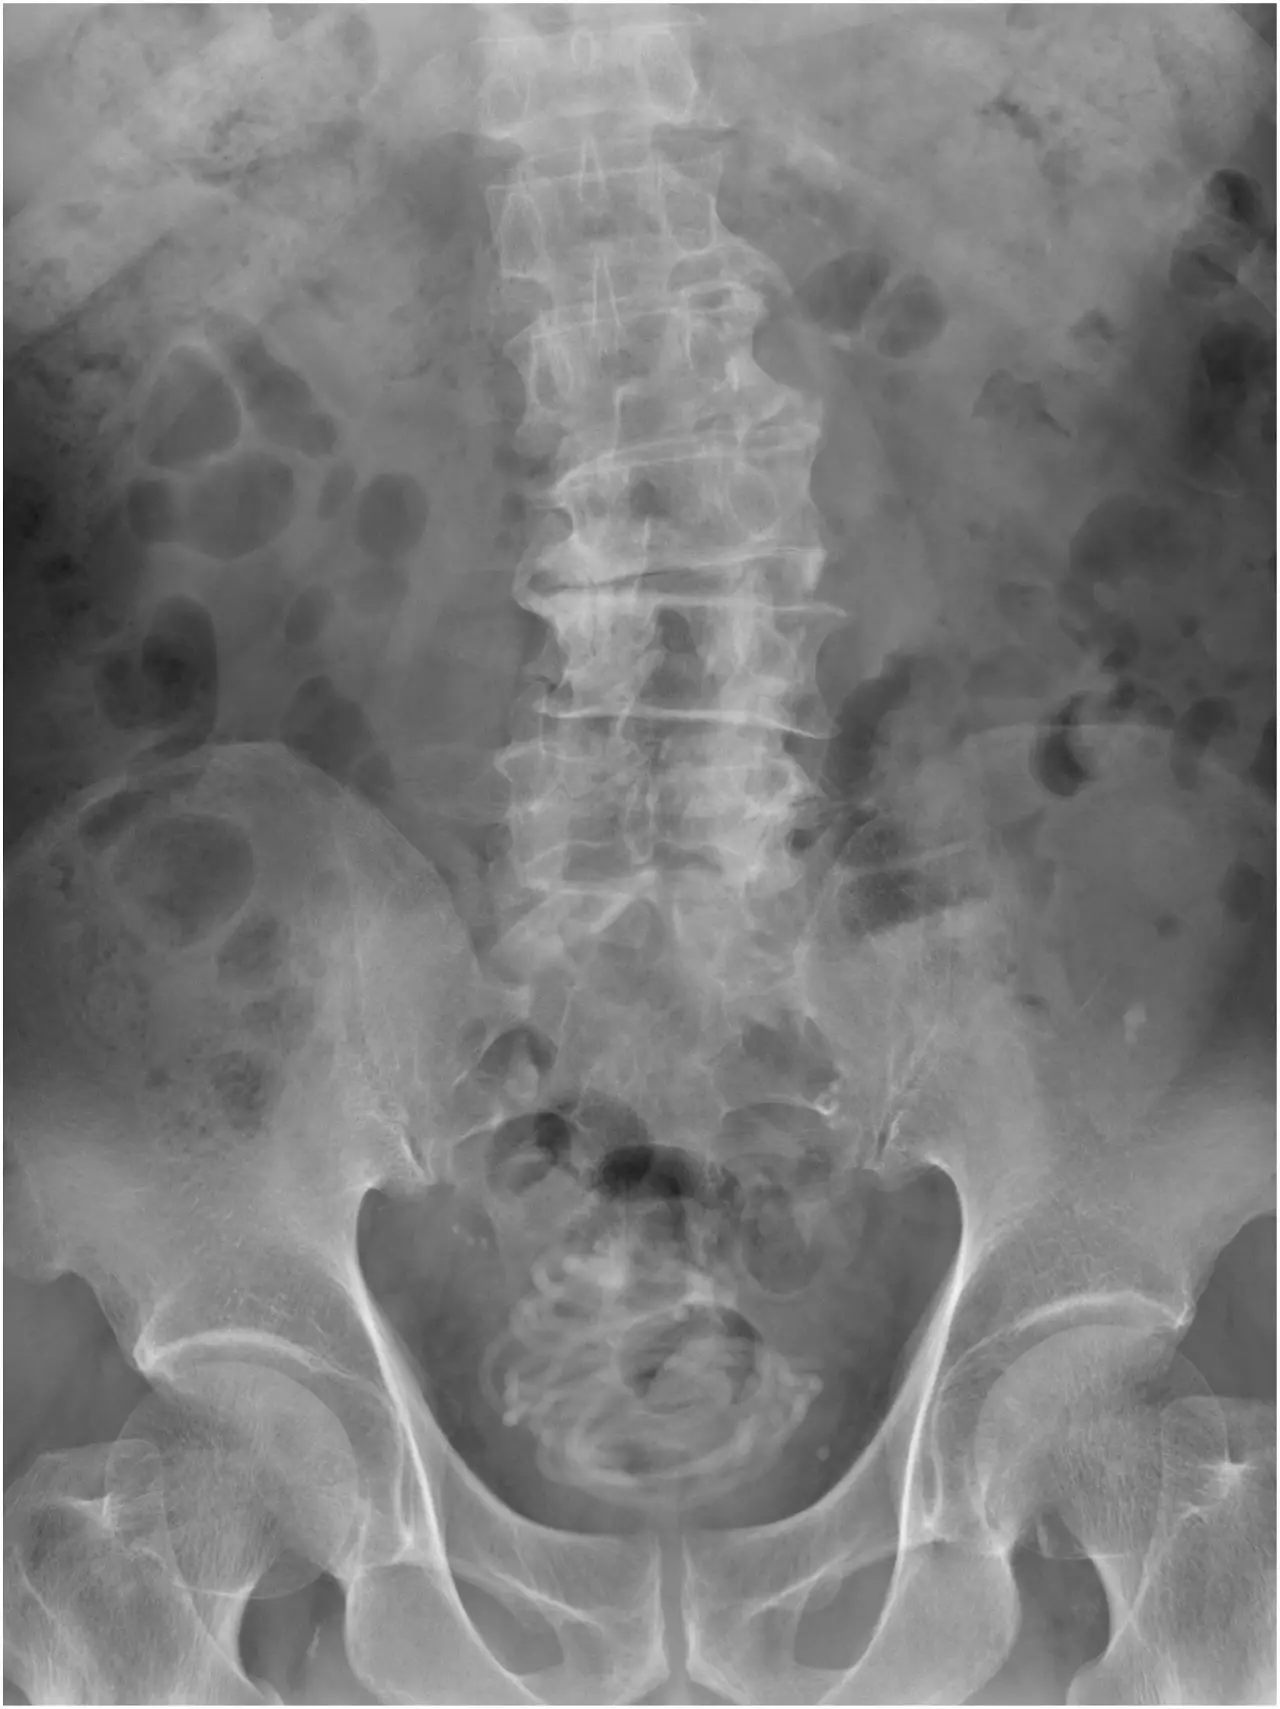

Legenda: Imagens obtidas pela equipe médica

Foto: Reprodução/Urology Case Reports